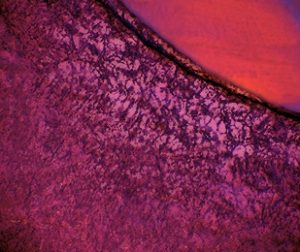

La microscopie à séchage par lyophilisation (FDM) fonctionne en observant le comportement structurel d'un échantillon tout en le séchant au microscope optique. Si la lyophilisation a pour but de produire un produit final stable, le FDM a au contraire le même objectif ; provoquer l’effondrement du produit et mesurer à quel le moment il se produit.

La FDM n’était traditionnellement utilisée que pour déterminer les températures d’effondrement, mais les équipements de dernière génération permettent également d’identifier les phénomènes de cristallisation, le potentiel de formation de peau / croûte et les effets du recuit sur la croissance des cristaux de glace et la structure du soluté.